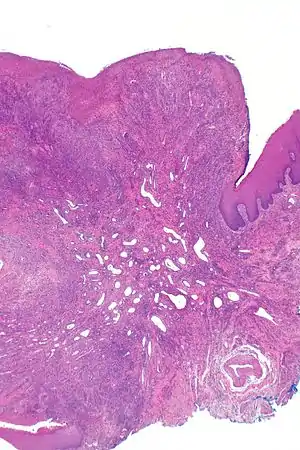

![]() | |

| Eosinophilic ulcer of the oral mucosa – H&E stain | |